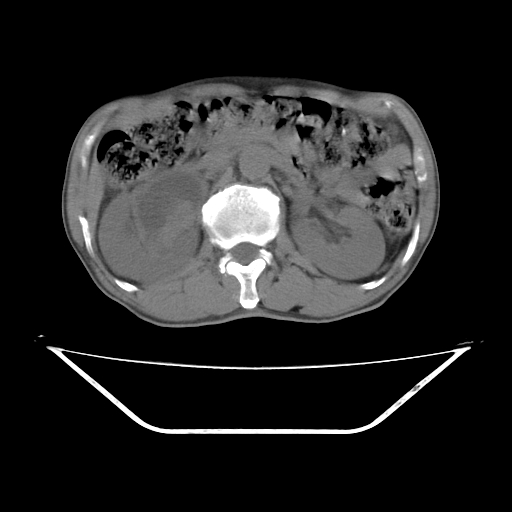

增强

考虑右侧肾盂癌。右侧输尿管扩张未扫描完。

右肾盂癌,肾动脉受侵,右肾盂输尿管积水,管壁增厚,考虑种植转移

右肾盂移行细胞癌并右输尿管中段转移.肾积水.

1.右侧肾盂癌伴肾盂积水。

2.肾脏功能减退,原因有:(1)肾动脉受侵。(2)肾静脉受侵(3)肾积水,等。本例,肾动脉显影较好,但受压明显;肾静脉无明显显示,受压或静脉癌栓,下腔静脉腔内未见明显充盈缺损。

3.右侧上段输尿管扩张,原因:(1)积水所致;(2)种植。